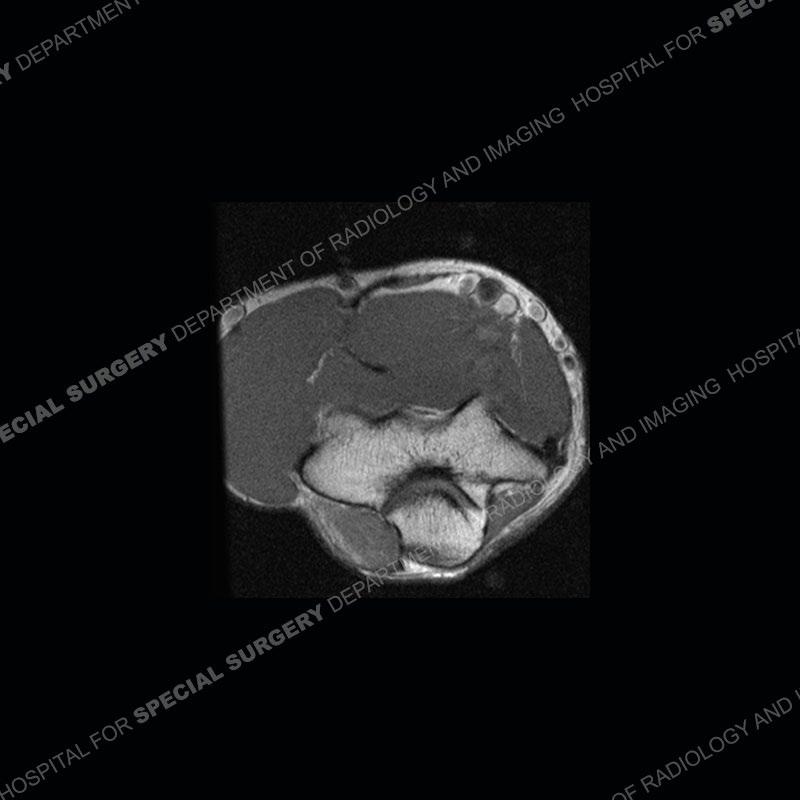

The radiographs are normal. On the MRI, the ulnar nerve has enlarged and T2 hyperintense fascicles proximal to and as it traverses the cubital tunnel. Just distal to the triceps attachment, a muscle is seen of the medial elbow, effacing the fat of the cubital tunnel and causing mass effect of the traversing ulnar nerve.

Diagnosis: Ulnar Nerve Compression from Anconeus Epitrochlearis

The anconeus epitrochlearis is considered an accessory muscle although it may have served some purpose in the ancient past. In most individuals it has become attenuated to form the roof of the cubital tunnel or Osborne’s ligament. In some individuals, the muscle persists and can cause an effacement of the fat of the cubital tunnel and it’s contents, the ulnar nerve. Just distal to the medial head of the triceps insertion, there should be fat present of the ulnar nerve and no muscle. The anconeus epitrochlearis may at times be associated with hypertrophy of the medial head of the triceps which can contribute to the mass effect upon the cubital tunnel and the ulnar nerve.

These patients may or may not be symptomatic. In this case, one can see the enlargement and T2 hyperintensity of the fascicles of the ulnar nerve. The imaging findings of the ulnar nerve do however remain somewhat nonspecific. There is a broad range of reported prevalence in the population but probably around 15% and with a relatively high frequency of bilaterality. In symptomatic patients, conservative measures can be attempted but unfortunately frequently fail. The surgical treatment is still debated as relates to releasing the muscle (myotomy), excision of the muscle (myomectomy), medial epicondylectomy, and the role of nerve transposition.